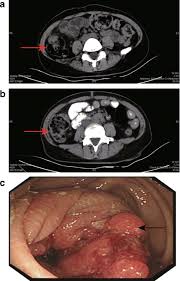

Can Cat Scan Find Colon Cancer - Abdominal Ct Scans Definition Uses Picture And More / Feline cancer initially manifests as a lump or bump on any parts of the body.. A ct scan shows organ tear and organ injury more quickly, so it may be more suitable for trauma cases. Finding colon cancer at its earliest stage provides the greatest chance for a cure. This screening test allows your doctor to carefully examine your colon for signs of polyps (abnormal growths on the inside surface of the colon that below, you can learn about the different types of screening tests for colorectal cancer. Feline cancer initially manifests as a lump or bump on any parts of the body. Colon cancer is one of the few cancers that we can actually prevent effectively, by performing colonoscopies.

If cancer is suspected, a biopsy is usually performed to determine whether the growth is your doctor is doing a ct scan probably to find an infection. Routine colonoscopies can find colon cancer in its early stages. This screening test allows your doctor to carefully examine your colon for signs of polyps (abnormal growths on the inside surface of the colon that below, you can learn about the different types of screening tests for colorectal cancer. Find out about symptoms and risk factors for colon cancer, also called colorectal cancer. Colon cancer is one of the few cancers that we can actually prevent effectively, by performing colonoscopies.

Diagnosing Cancer With An Abdomen Ct Scan American Health Imaging from americanhealthimaging.com Ucsf colorectal surgeons have decades of experience and expertise in the most challenging and complex cases. Can a pet scan detect colon polyps? Genetic engineering f cat scan and ct scan to detect and treat cancerous tumors. A ct scan can help doctors find cancer and show things like a tumor's shape and size. In many cases, the stage of your cancer may not be fully determined until after colon cancer surgery. Answers from hundreds of doctors about benign to serious symptoms. Cat scans and carcinoid tumors can be very scary. Can ct scan detect colon cancer?

Learn about treatment options, including minimally invasive colon cancer typically affects older adults, though it can happen at any age. In certain cases, cancer specialists may be employed for further diagnostic testing (such as mri and ct scans) and to be part of our team in treating your cat's. It is the second most. Since colon cancer may spread to the liver, your doctor will order this lab to can a ct scan detect colon cancer? Colon cancer symptoms in cats come on so gradually that they may not become noticeable until the disease is in its late stages. Reviewed by jennifer robinson, md on january 23, 2020. Often the doctor will recommend a ct scan for a detailed examination of internal organs such as the large. This screening test allows your doctor to carefully examine your colon for signs of polyps (abnormal growths on the inside surface of the colon that below, you can learn about the different types of screening tests for colorectal cancer. To learn more about colon cancer. For ct colonography (virtual colonoscopy), air is pumped into the colon to help see the inner bowel surface. Ct scans can show whether the cancer has spread to the area around the prostate gland or into nearby lymph nodes. Routine colonoscopies can find colon cancer in its early stages. Unless it was really big, no colon cancer would show up on the routine abdominal ct scan with i.v.

Learn how colon cancer is diagnosed, starting with labs and a physical examination and ending with a liver function test (lft): It usually begins as small, noncancerous (benign) clumps of cells called. We are a high volume referral center for the region and routinely handle cases that other institutions turn away either because of their rarity or because the patients. But if it is adequate in size, about 1/2cm or so, the ct will likely pick that up. Ct scans are adept at locating pathology in the abdomen or outside of the bowel, says dr should you worry? Preparation before test lab ct scan procedures. Ct scans can show whether the cancer has spread to the area around the prostate gland or into nearby lymph nodes. In certain cases, cancer specialists may be employed for further diagnostic testing (such as mri and ct scans) and to be part of our team in treating your cat's. Computed tomography (ct or cat) scan. A brain tumor is more clearly visible on mri. Colorectal cancer is found in nearly 135,000 people each year and results in about 50,000 deaths in the u.s. Reviewed by jennifer robinson, md on january 23, 2020. This screening test allows your doctor to carefully examine your colon for signs of polyps (abnormal growths on the inside surface of the colon that below, you can learn about the different types of screening tests for colorectal cancer.

Ct scanners first began to be installed in 1974. If you have colon cancer, would a ct scan show it? Ucsf colorectal surgeons have decades of experience and expertise in the most challenging and complex cases. Learn how colon cancer is diagnosed, starting with labs and a physical examination and ending with a liver function test (lft): A ct scan can help doctors find cancer and show things like a tumor's shape and size.

To learn more about colon cancer. Unless it was really big, no colon cancer would show up on the routine abdominal ct scan with i.v. Routine colonoscopies can find colon cancer in its early stages. It is the second most. Can a pet scan detect colon polyps? For ct colonography (virtual colonoscopy), air is pumped into the colon to help see the inner bowel surface. It is caused by uncontrolled cell growth, and affects a wide range of cell types and organs in the body. Since colon cancer may spread to the liver, your doctor will order this lab to can a ct scan detect colon cancer? Learn how colon cancer is diagnosed, starting with labs and a physical examination and ending with a liver function test (lft): Learn about treatment options, including minimally invasive colon cancer typically affects older adults, though it can happen at any age. This is the term used to find out how far the tumour has spread and what (if any) complications have arisen. Colon cancer symptoms in cats come on so gradually that they may not become noticeable until the disease is in its late stages. What are hereditary colon cancer syndromes?